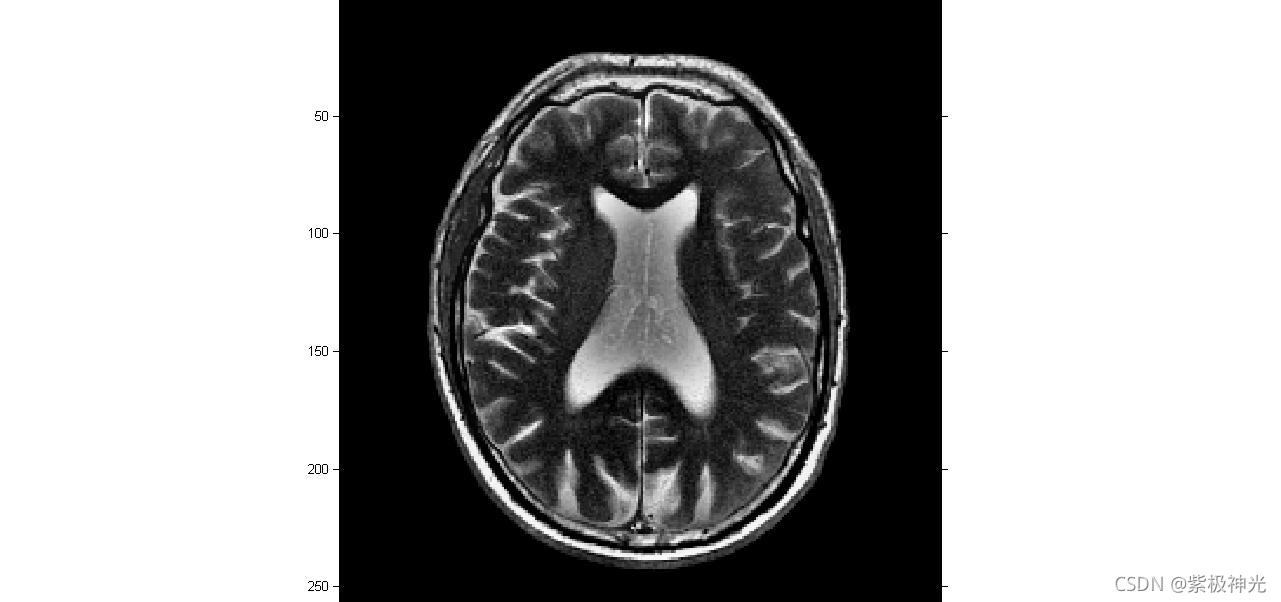

三、运行结果